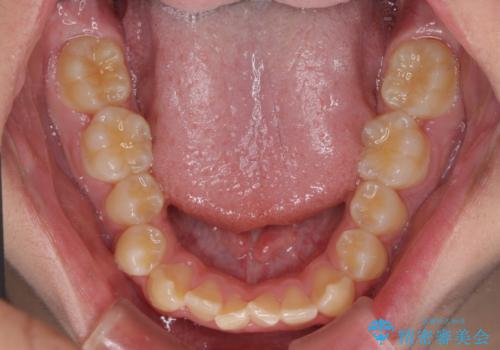

しっかり使って短期間で治療 インビザラインによる叢生解消

「しっかりと装着する」が実行でき、高校3年生の秋には治療を終えることができました。

入試時期に入ると、後戻り防止のリテーナー装着が疎かになる可能性があったり、リテーナーが壊れてしまった場合すぐに来院できなかったりというリスクがあったため、下顎前歯の舌側をワイヤーで固定することとしました。